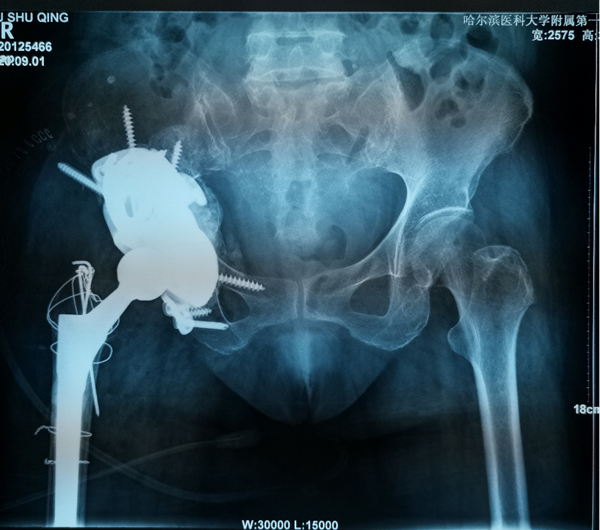

对于复杂髋关节翻修多为高龄患者,由于骨缺损巨大、骨质疏松等因素,存在手术难度大、手术费用高等难题。近日,ac米兰官网中文网站一院骨科一病房3D打印团队,应用3D打印技术,通过术前打印骨骼模型进行模拟假体安装,成功为一名70岁全髋关节置换术后15年,髋臼骨缺损巨大,髋臼上部坐骨、髂骨存在巨大空洞型缺损的患者实施了我省首例金属3D打印三翼髋臼假体(Triflange)+股骨柄假体髋关节翻修术,为患者更换了一个新的、稳定的髋关节。目前患者已康复出院。

70岁的刘阿姨15年前因股骨头坏死进行了全髋关节置换手术。五年前右腿开始有明显的缩短,髋部疼痛也逐渐加重,来到ac米兰官网中文网站一院时已经无法行走。经影像检查,患者15年前采用水泥固定髋臼杯,金属头和聚乙烯髋臼杯十数年的摩擦产生的聚乙烯碎屑已经导致髋臼巨大的骨缺损,假体上移,不仅髋臼,甚至坐骨、髂骨都有骨溶解,属于Paprosky·3B型髋臼侧骨缺损。此类疾病的治疗主要采用三翼髋臼假体(Triflange)。由于患者髋臼骨缺损巨大,特别是在髋臼上部存在巨大的空洞型缺损,传统的Triflange假体不能满足刘阿姨髋臼的稳定支撑和重建,且患者骨质疏松,传统假体骨长入能力难以满足要求。

骨科一病房数字骨科负责人耿硕教授在详细了解患者情况后,决定为患者进行个性化的金属3D打印技术。定制化3D打印髋臼Triflange假体相比于传统假体有以下优点: 3D打印Triflange假体三个翼面通过螺钉分别固定在髂骨,耻骨和坐骨上提供了稳定的初始固定;金属3D打印拥有更好的孔隙率,有助于后期骨长入稳定固定;个性化的术前设计,实现了垫块和臼杯一体的轻量化支撑,更好地填充上方骨缺损重建髋关节的稳定性,此外为应对术中可能的意外情况,还可3D打印不同大小的垫块。

为了确保手术顺利,手术前耿硕根据患者的影像数据,经过三维重建,真实复原了患者的右髋关节和盆骨模型。借助这一模型,耿硕可以全面精准地了解患者的关节结构,骨质情况等重要信息,为术前制订精确的手术方案提供了重要依据。手术当日,耿硕手术团队按照术前模拟,顺利的将金属假体精准地安放在髋关节内。经过一周的康复,患者已顺利下地行走并康复出院。